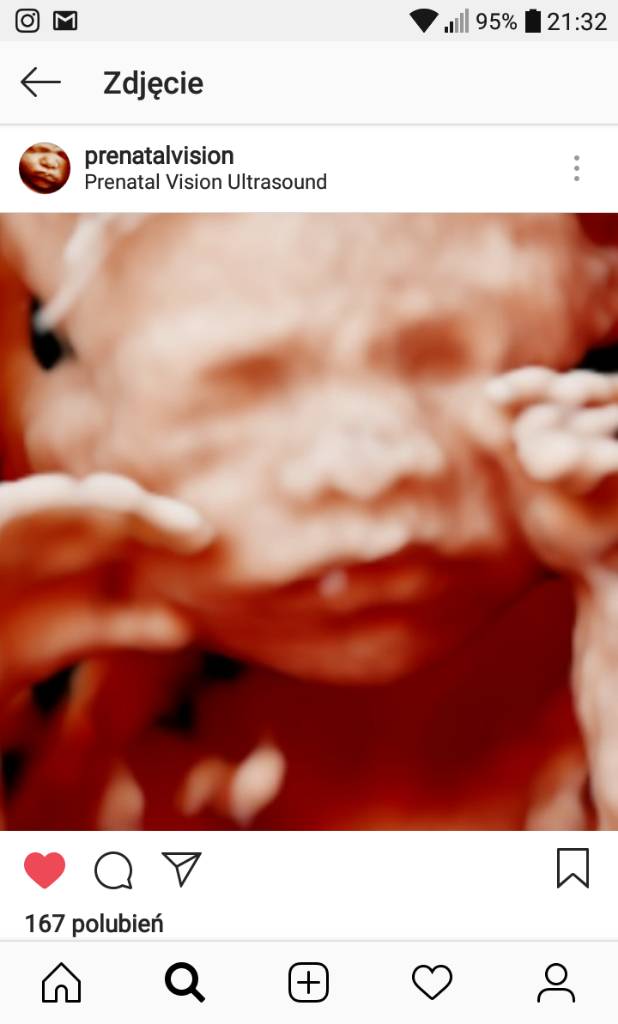

Co do fotek 3d to i Nicole Mamaginekolog wrzuca i mówi, że najładniej buzię widać ok. 30 tygodnia.

Obserwuję też na insta prenatalvision i wrzucę od nich foty. Zobacz sama. Tu 22 i 32 tydzień ciążyZobacz załącznik 878576Zobacz załącznik 878578Zobacz załącznik 878579Zobacz załącznik 878581

Rzeczywiście, piękne te fotki w okolicy 30tygodnia! Jak zdjęcie